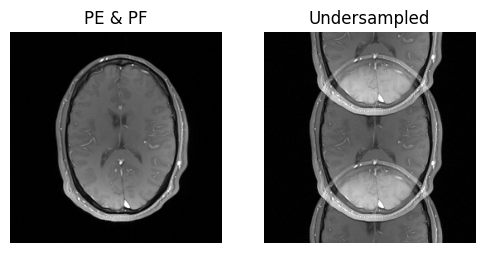

show_images(idat_pe_pf.rss().squeeze(), idat_us.rss().squeeze(), titles=['PE & PF', 'Undersampled'])

../_images/d237da143177310653ed25577e9849c1ab994d0aceaf8a083e44f5924e69c87c.png